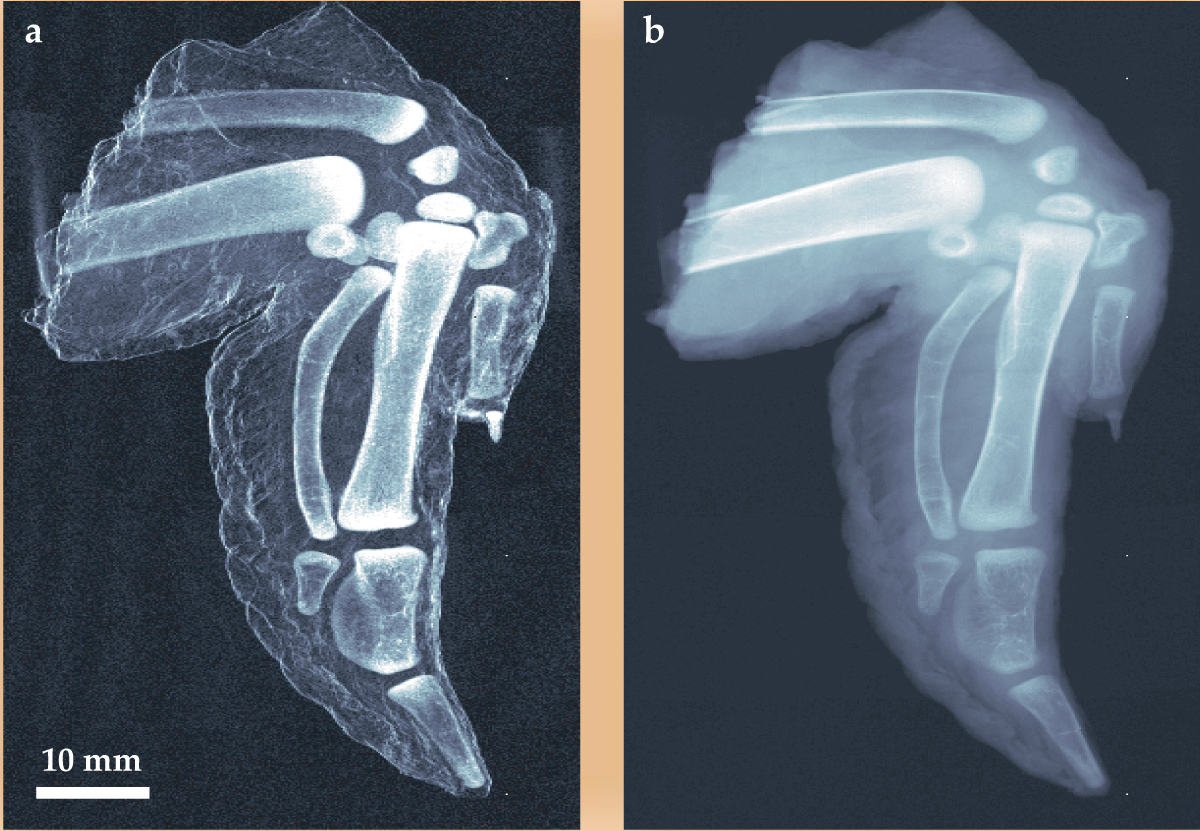

Figure 2(a), the PSI group’s dark-field image of a chicken wing, demonstrates the technique’s potential for improved contrast in medical imaging. The image is a map of V(m,n) created from the fitted Fourier parameters. It effectively subtracts off the mean glare of unabsorbed, unscattered x rays from the source. In the blackest regions of the image, the visibility function is the same as it is with no sample, and the whitest regions are where V is most diminished by scattering in the sample. In the sense that figure 2(a) is an analytically processed construct based on several interferometric exposures, it is a less direct dark-field image than one gets with crystal manipulation of an x-ray beam at an accelerator light source.

Figure 2. X-ray images of a chicken wing. (a) Dark-field image is a pixel-by-pixel plot of the visibility function V of the interference fringes at the detector in figure

(Adapted from ref. 2.)

For comparison, figure